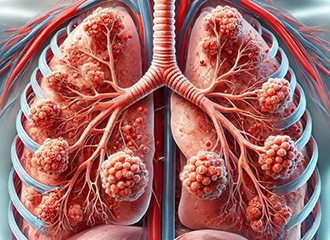

Verbesserung der Frühdiagnose von Asthma bei Kindern

Asthma ist die häufigste chronische Erkrankung im Kindesalter. Bisher konnte sich aber kein einheitlicher Test zur Diagnose bei kleinen Kindern etablieren, viele werden wegen einer nicht korrekten Diagnose unter- oder überbehandelt. In diesem Projekt wollen die Empa-Forschenden gemeinsam mit dem Universitäts-Kinderspital Zürich eine neue Diagnose von Asthma bei Vorschulkindern entwickeln. Dazu untersuchen sie die Moleküle in der ausgeatmeten Luft und identifizieren Asthma auslösende Gene. Parallel dazu werden öffentlich zugängliche Datensätze aus mehreren früheren Studien beschafft und mit Hilfe von Datenanalyse vorhergesagt, welche Genvarianten Asthma bei Kleinkindern wahrscheinlich verursachen. Die Rolle dieser Gene in Immunzellen wird anschliessend experimentell untersucht. Die Einschätzung der genetischen Veranlagung, zusammen mit der Erkennung spezifischer Moleküle im Atem, haben das Potenzial, die bestehende klinische Praxis zu verbessern. Ausserdem würde die erfolgreiche Validierung der molekularen Signalnetzwerke zusätzlich neue Wege in Richtung therapeutischer Interventionen eröffnen.

Die Mirto Stiftung sowie eine weitere Stiftung haben das Projekt bereits grosszügig unterstützt. Derzeit werden jedoch noch weitere Mittel gesucht.